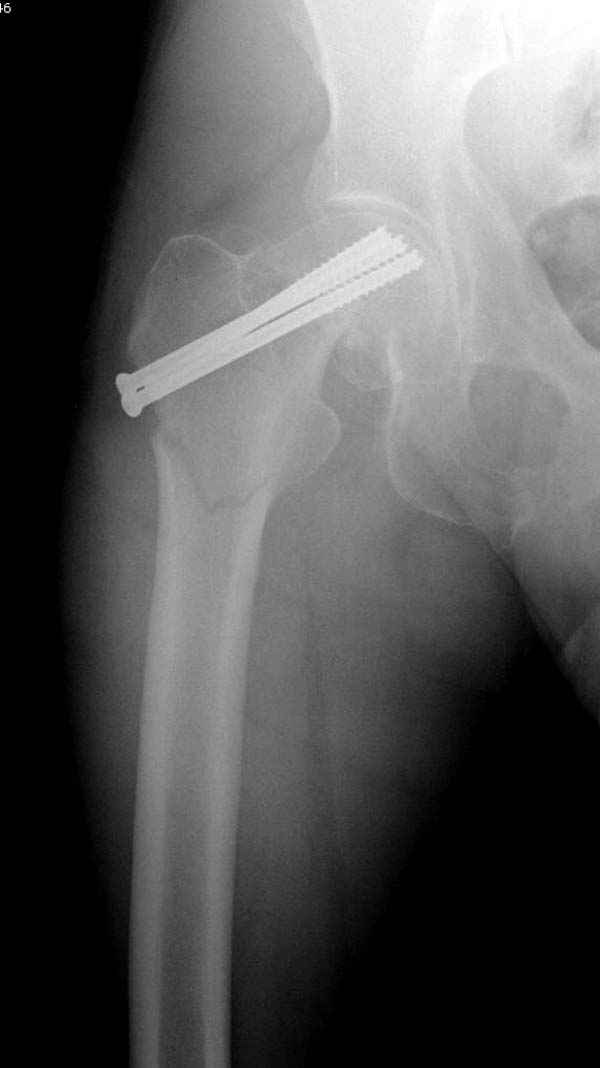

На второй день после выписки упал дома. Снимки приложены. Коллеги рекомендуют удаление шурупа и вытяжение. Что делать?

Правильно, ситуация изменилась, как говорят у нас теперь "different animal", надо решать проблему подвертельного перелома. При наличии различных вариантов фиксаторов, включая Страйкер Гамма 3, мы выбрали DePuy Antegrade Trachanteric Nail из-за многовариантности проксимальной фиксации и двойного изгиба. Вводится через вертел под 8 градусным углом, и есть достаточный передний диафизарный изгиб, предупреждающий пенетрацию дистального переднего кортекса.

Но ведь и головка бедра сползла в варус - отчего ограничились только фиксацией подвертельного перелома, а не убрали винты и не сделали репозицию шейки?